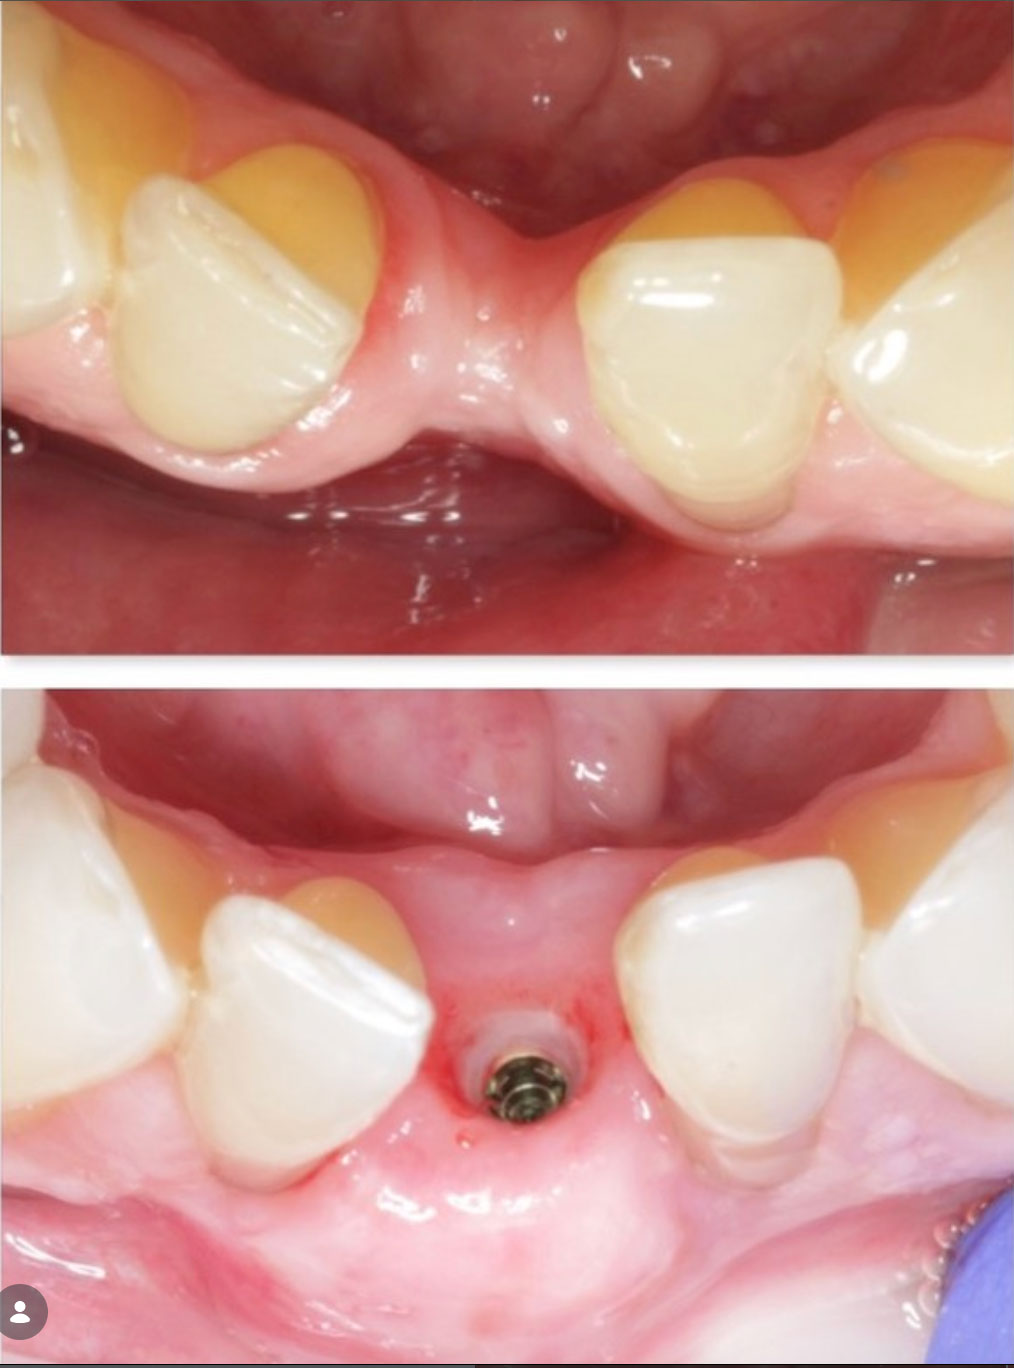

Before & Afters of Dental Implant Patients

Complete Dental Implant Cases Gallery

• During the first stage of surgery, your dentist or specialist will put a dental implant into your jawbone beneath the gum tissue. The gum tissue is then stitched back into place. As the tissue heals, the implant will bond with the bone and attach to the gum. It can take several months to heal.

• During the second stage of surgery and once the tissue is healed, your dentist or specialist will attach an abutment to the implant. An abutment is a post that connects the replacement tooth to the implant. In some cases, the first and second stage of implant surgery may be done in one single stage.

General Disclaimer: The results in the photographs are examples only and do not imply any certainty of the result of a procedure, and all outcomes are subject to the circumstances of the individual patient.